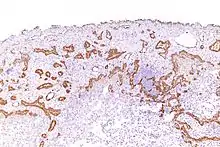

Micrograph of a malignant epithelioid mesothelioma stained with an antibody against calretinin.

Mesothelioma

Using immunohistochemistry, calretinin can be demonstrated in both benign mesothelium and in malignant mesothelioma[12][13] and can be used to help differentiate different lung tumours.[14] Antibodies to calretinin can also be used to distinguish between different types of brain tumour, demonstrating only those with neuronal rather than glial, differentiation.[15] Furthermore, the essential function of calretinin in mesothelioma cell lines has been demonstrated in vitro and may be an interesting target for therapeutical approaches.[16]